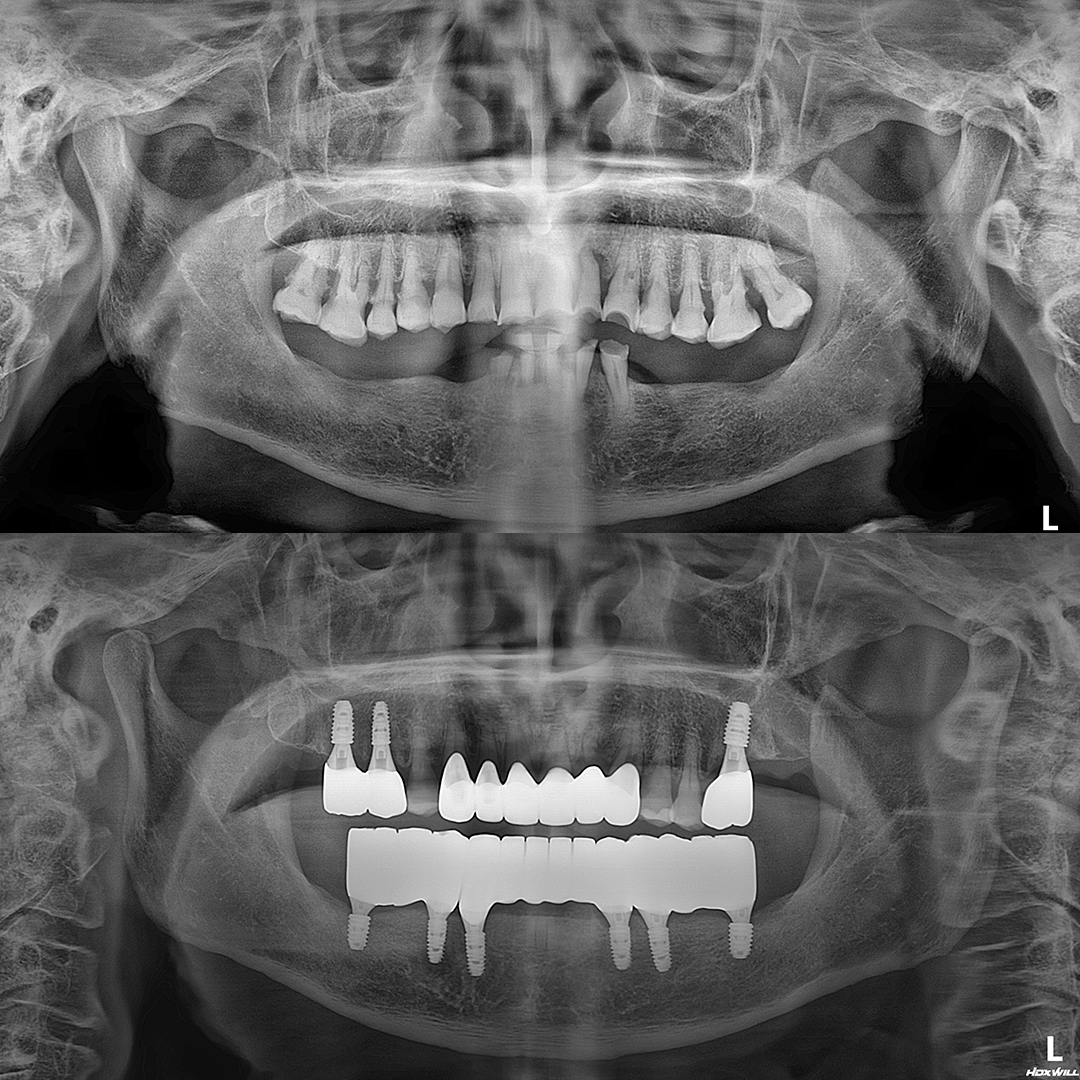

발치와 임플란트 시술이 단 하루만에!

원데이 임플란트

단 한번의 수술만으로 발치와 동시에

즉시 임플란트를 식립하여 불편감을 줄이고 치료기간을 단축할 수 있습니다.

자연치아는 최대한 보존하고 빠른 회복을 위한

최소침습 임플란트

풍부한 임상경험을 토대로 잇몸뼈를 절개하지 않고

빠르고 정확하게 임플란트를 식립하여 붓기와 통증을 최소화합니다.